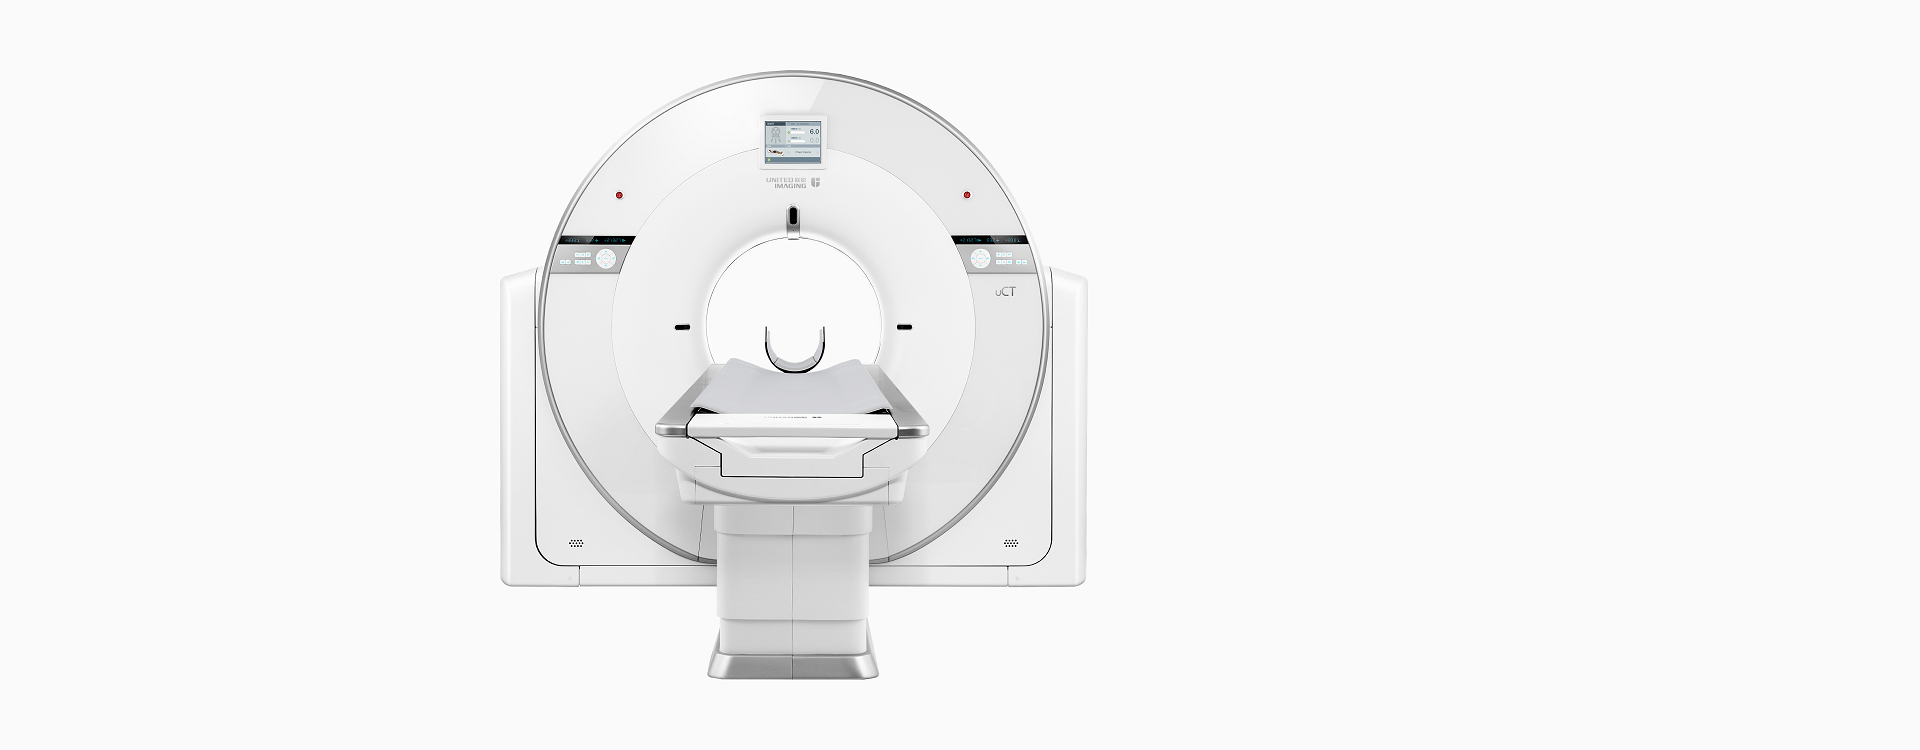

高端硬件

5.3MHU

大热容量球管,轻松应对高通量检查

50kW

大功率高压发生器,带来源源不断的澎湃动力

40排时空探测器

22mm覆盖,0.55mm层厚,卓越空间分辨率与密度分辨率兼而得之

70kV扫描模式

大幅降低辐射剂量,提高造影剂对比度,使微小病变等临床应用难点被突破